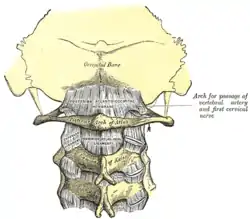

The posterior part of the arch presents above and behind a rounded edge for the attachment of the posterior atlantooccipital membrane, while immediately behind each superior articular process is the superior vertebral notch (sulcus arteriae vertebralis). This is a groove that is sometimes converted into a foramen by ossification of the posterior atlantooccipital membrane to create a delicate bony spiculum which arches backward from the posterior end of the superior articular process. This anatomical variant is known as an arcuate foramen.

This groove transmits the vertebral artery, which, after ascending through the foramen in the transverse process, winds around the lateral mass in a direction backward and medially to enter the vertebrobasilar circulation through the foramen magnum; it also transmits the suboccipital nerve (first spinal nerve)